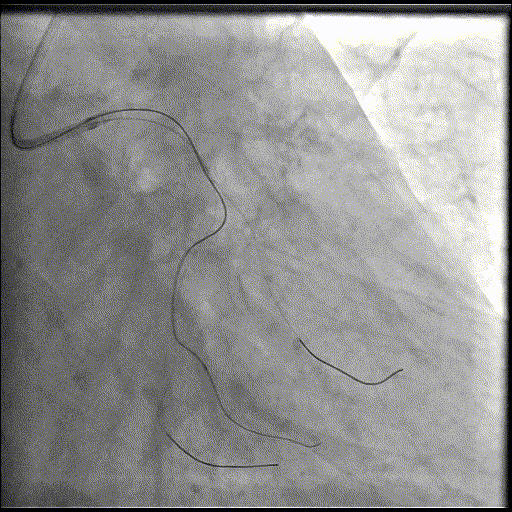

病例三

朱天奇教授

创新性二次干预:IVL修正支架植入术后贴壁不良。

基本情况:患者,男,73岁,因“活动后突发持续性胸痛”入院。既往高血压、糖尿病病史,血脂异常(LDL-C 3.94mmol/L)。

简要病史:患者曾于2025年4月因急性下壁心肌梗死,急诊行PCI治疗,于RCA植入1枚支架。本次入院计划处理LAD。

辅助检查:EKG:下壁导联Q波,T波倒置;UCG:左室下壁收缩活动减弱,LVEF 57%。

基础造影

右冠状动脉近段基本正常,中段狭窄50%,远段原支架通畅,右冠-后降支开口狭窄70%;左主干狭窄40%;前降支近中段全程弥漫性钙化病变,狭窄80-99%,第一对角支狭窄60%,第二对角支狭窄80%;回旋支近段基本正常,远段狭窄60%。

手术经过

导丝到位

当指引导管冠脉开口到位后,选择三根对应导丝分别送入LAD、D1、D2远端。

球囊预扩

选择不同尺寸的预扩球囊逐级预扩张病变,复查造影狭窄减轻不明显。为了解血管真实情况,遂启用IVUS检查。

术前腔内影像学IVUS指导

IVUS提示血管内钙化严重,最小管腔面积不足 4mm²;遂考虑启动IVL治疗。

冲击波球囊治疗

2.5*12mm@4atm 冠脉血管内冲击波导管反复进行8个周期治疗,经IVUS检查提示最小管腔面积增加至4.88mm²;随后选取后扩张球囊对病变行扩张治疗。

支架植入并后扩

于LM-LAD依次植入两枚药物洗脱支架,经非顺应性球囊后扩张支架,复查造影&IVUS提示血管内钙化仍较重,支架贴壁不良,遂再次启动IVL治疗。

再次冲击波球囊治疗

3.0*12mm@4atm 冠脉血管内冲击波导管反复进行5个周期治疗,并选取后扩张球囊对病变行扩张治疗。最终复查造影提示残余狭窄小于10%,未见夹层及血肿,TIMI血流3级。